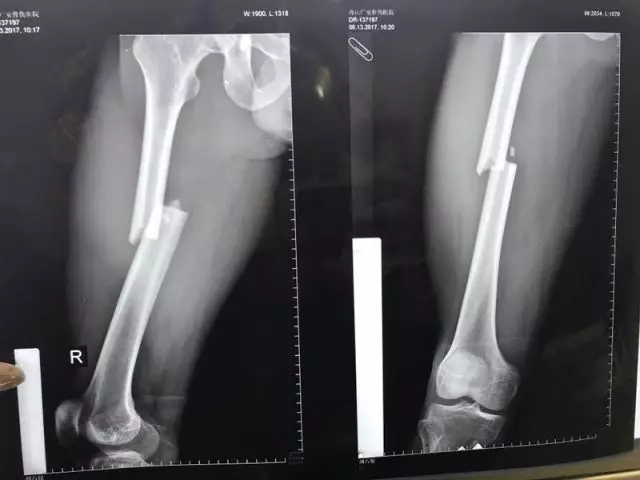

患者入院后進(jìn)行了一系列檢查,發(fā)現(xiàn)股骨干處的粉碎性骨折塊移位特別明顯,下肢出現(xiàn)了短縮、外展畸形,大腿非常腫脹,內(nèi)出血很多,患者十分痛苦。

▲ 幾個(gè)微創(chuàng)小切口即可完成手術(shù)